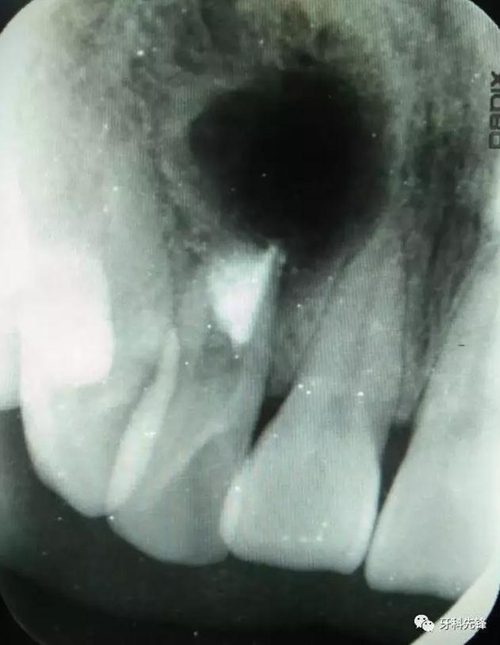

圖1.術(shù)前的根尖片影像檢查:12根管粗大、根尖未形成。根尖下方有一橢圓形囊腔,囊內(nèi)有牙。

圖20.術(shù)后的根尖片影像檢查,根尖區(qū)MTA封閉完好。